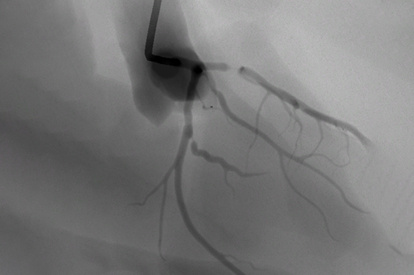

The ANGIO Mentor simulator is an essential tool for clinicians to practice and acquire the skills needed for performing endovascular interventions. Trusted by medical associations, hospitals, training centers, and the medical device industry globally, it provides trainees with realistic clinical settings to practice endovascular interventions using fluoroscopic and ultrasound guidance.

Offers true-to-life simulation of the clinical environment, including advanced imaging modalities like fluoroscopy/echocardiography, hemodynamic monitoring, medications, and interventional devices

Coronary Intervention Module

Transradial Coronary Intervention Module

Coronary Bifurcation Module

Coronary CTO Module